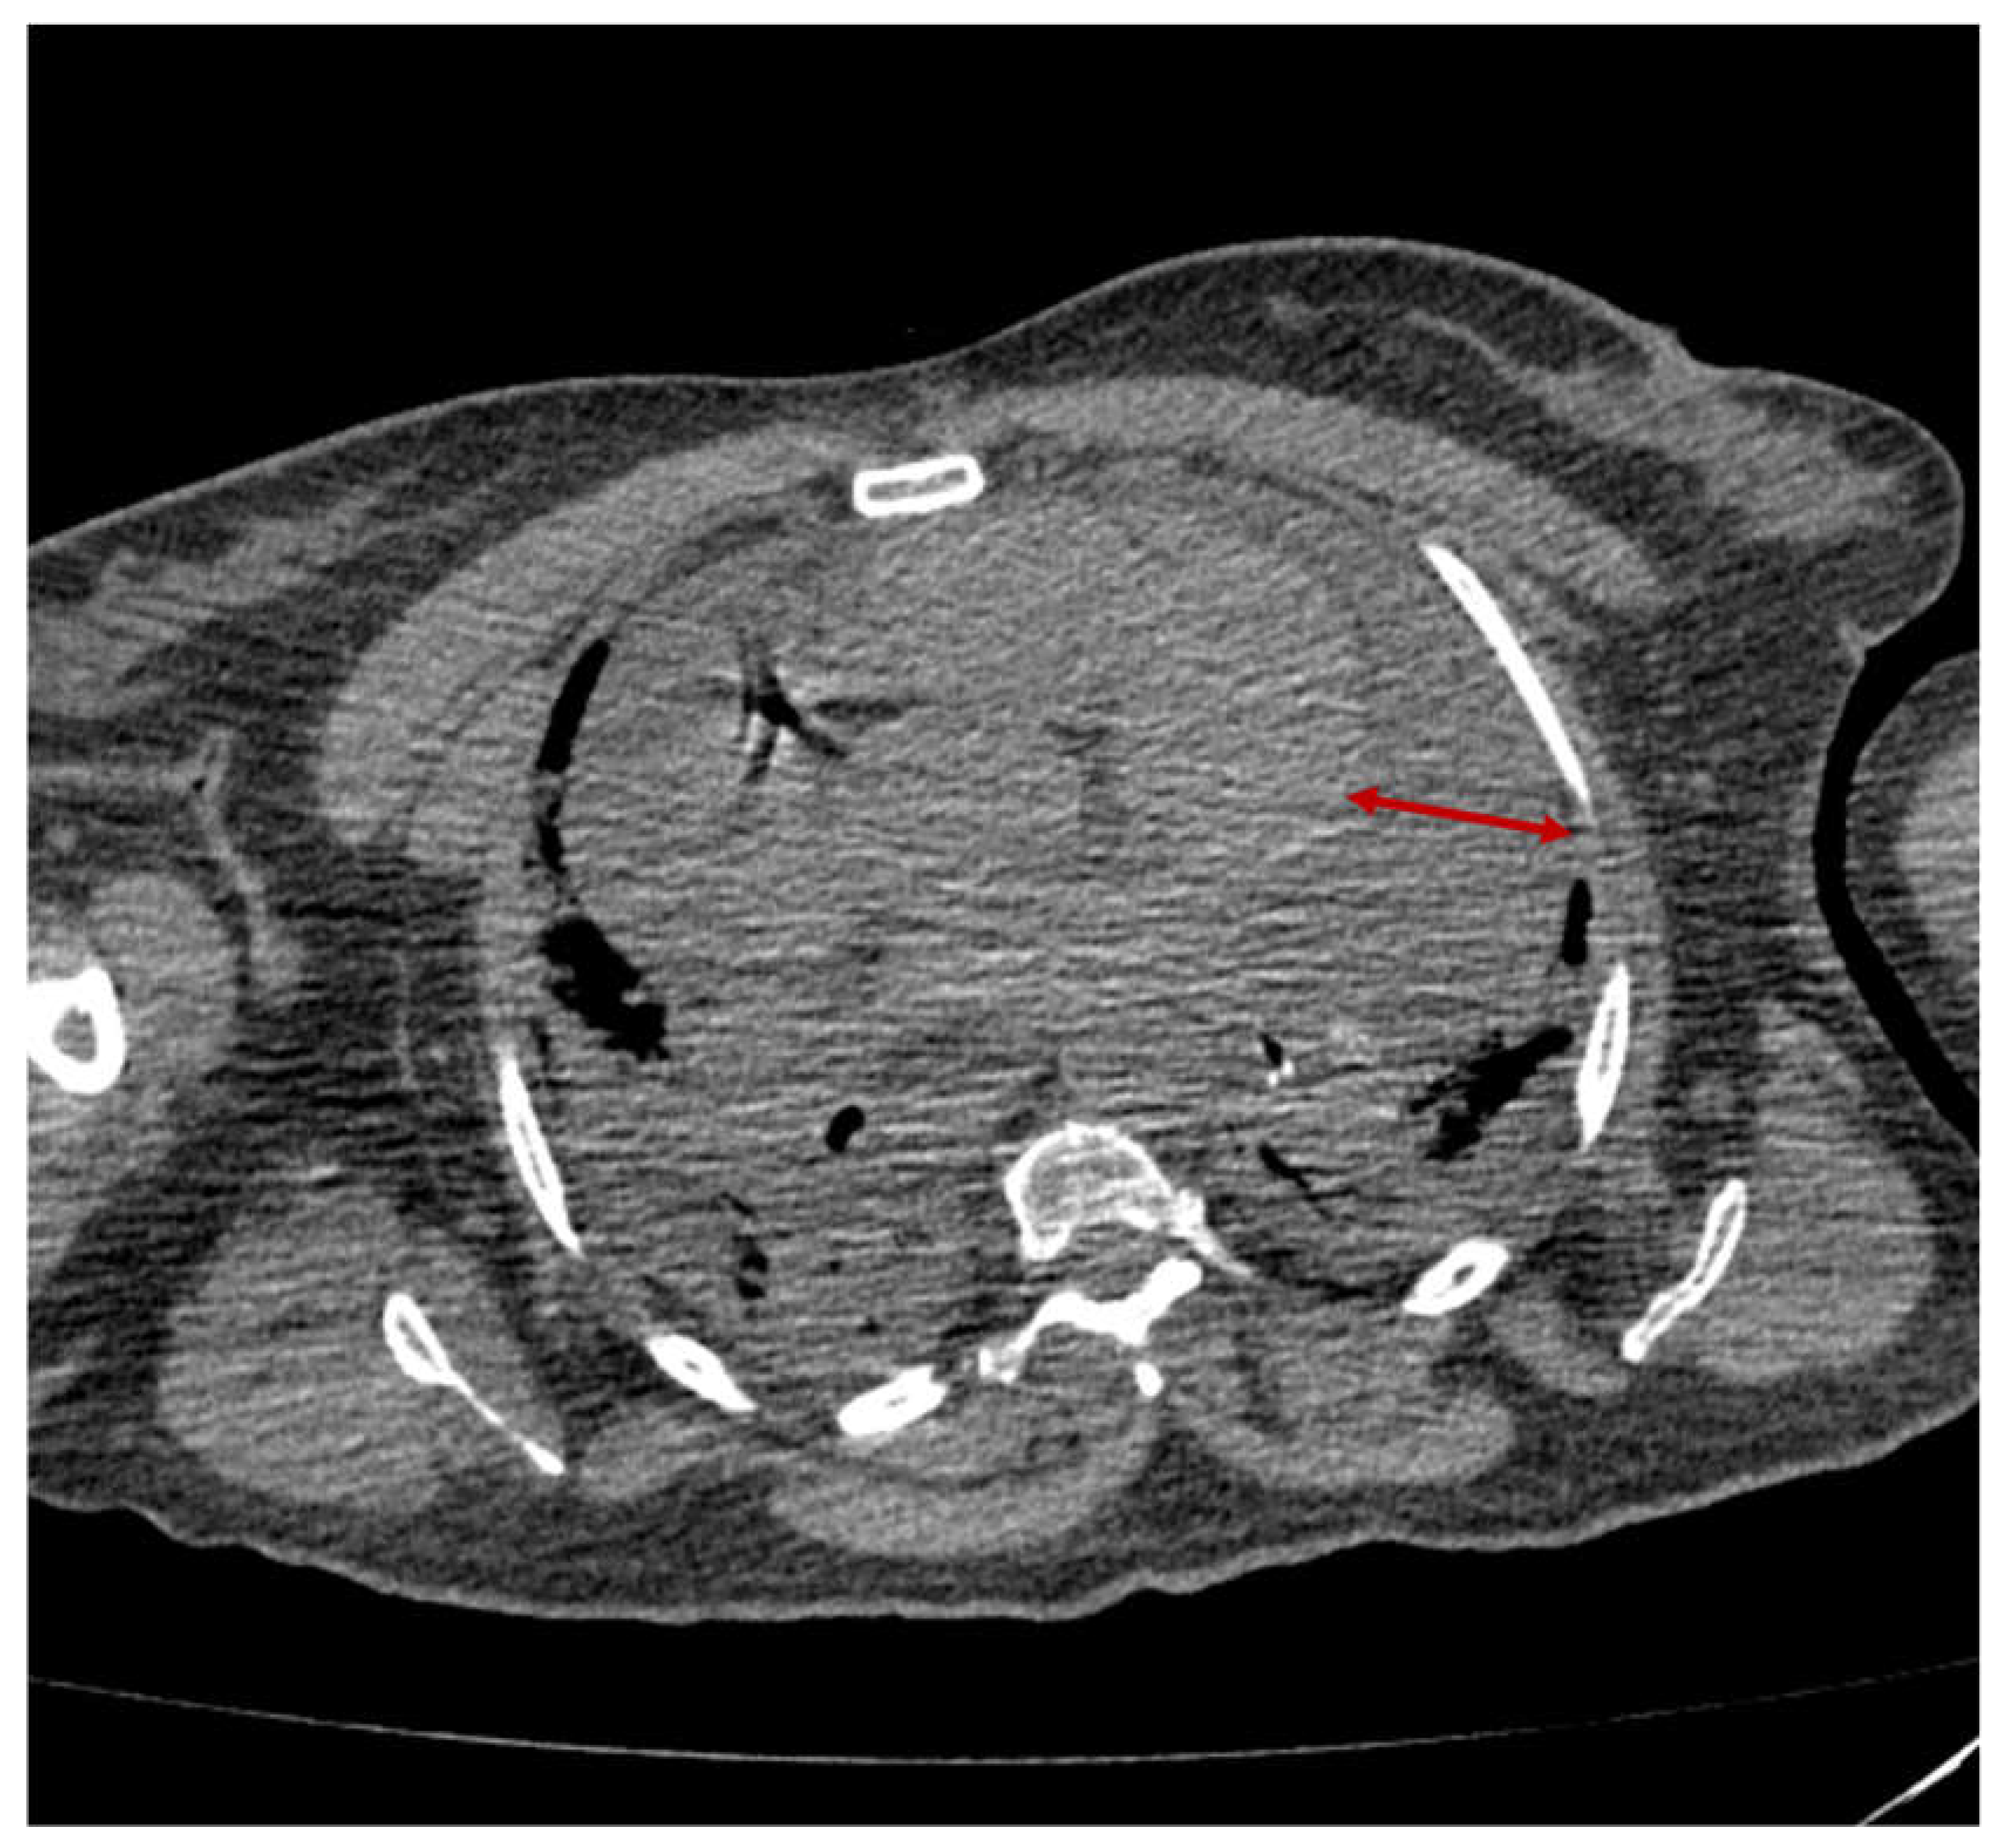

2.3. Case 3